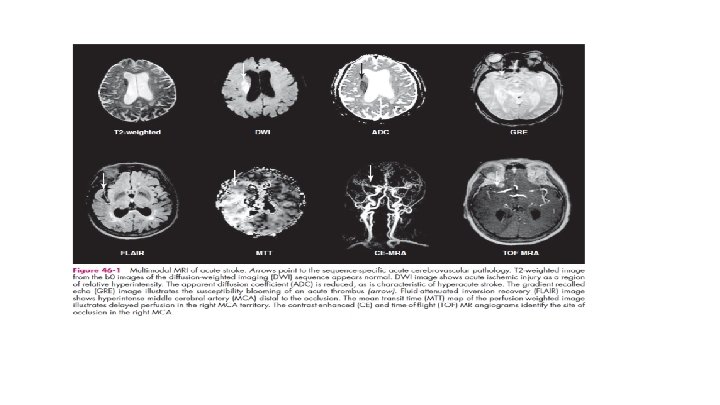

Acute Ischemic Stroke: Major thrombolytic Landmarks Lower rates of early recanalization and worse outcomes in patients with large vessel occlusion (LVO) with IV r-t. PA.

Acute Treatment – IA Therapy • Improved clot retrieval devices: • Stentrievers • Aspiration devices